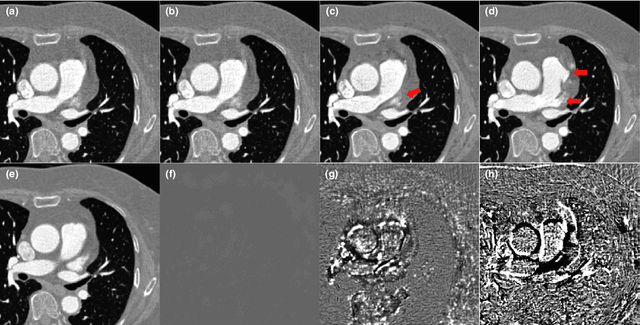

Abstract:Model based iterative reconstruction (MBIR) algorithms for low-dose X-ray CT are computationally expensive. To address this problem, we recently proposed a deep convolutional neural network (CNN) for low-dose X-ray CT and won the second place in 2016 AAPM Low-Dose CT Grand Challenge. However, some of the texture were not fully recovered. To address this problem, here we propose a novel framelet-based denoising algorithm using wavelet residual network which synergistically combines the expressive power of deep learning and the performance guarantee from the framelet-based denoising algorithms. The new algorithms were inspired by the recent interpretation of the deep convolutional neural network (CNN) as a cascaded convolution framelet signal representation. Extensive experimental results confirm that the proposed networks have significantly improved performance and preserves the detail texture of the original images.

Abstract:Due to the potential risk of inducing cancers, radiation dose of X-ray CT should be reduced for routine patient scanning. However, in low-dose X-ray CT, severe artifacts usually occur due to photon starvation, beamhardening, etc, which decrease the reliability of diagnosis. Thus, high quality reconstruction from low-dose X-ray CT data has become one of the important research topics in CT community. Conventional model-based denoising approaches are, however, computationally very expensive, and image domain denoising approaches hardly deal with CT specific noise patterns. To address these issues, we propose an algorithm using a deep convolutional neural network (CNN), which is applied to wavelet transform coefficients of low-dose CT images. Specifically, by using a directional wavelet transform for extracting directional component of artifacts and exploiting the intra- and inter-band correlations, our deep network can effectively suppress CT specific noises. Moreover, our CNN is designed to have various types of residual learning architecture for faster network training and better denoising. Experimental results confirm that the proposed algorithm effectively removes complex noise patterns of CT images, originated from the reduced X-ray dose. In addition, we show that wavelet domain CNN is efficient in removing the noises from low-dose CT compared to an image domain CNN. Our results were rigorously evaluated by several radiologists and won the second place award in 2016 AAPM Low-Dose CT Grand Challenge. To the best of our knowledge, this work is the first deep learning architecture for low-dose CT reconstruction that has been rigorously evaluated and proven for its efficacy.

Abstract:Model based iterative reconstruction (MBIR) algorithms for low-dose X-ray CT are computationally complex because of the repeated use of the forward and backward projection. Inspired by this success of deep learning in computer vision applications, we recently proposed a deep convolutional neural network (CNN) for low-dose X-ray CT and won the second place in 2016 AAPM Low-Dose CT Grand Challenge. However, some of the texture are not fully recovered, which was unfamiliar to some radiologists. To cope with this problem, here we propose a direct residual learning approach on directional wavelet domain to solve this problem and to improve the performance against previous work. In particular, the new network estimates the noise of each input wavelet transform, and then the de-noised wavelet coefficients are obtained by subtracting the noise from the input wavelet transform bands. The experimental results confirm that the proposed network has significantly improved performance, preserving the detail texture of the original images.